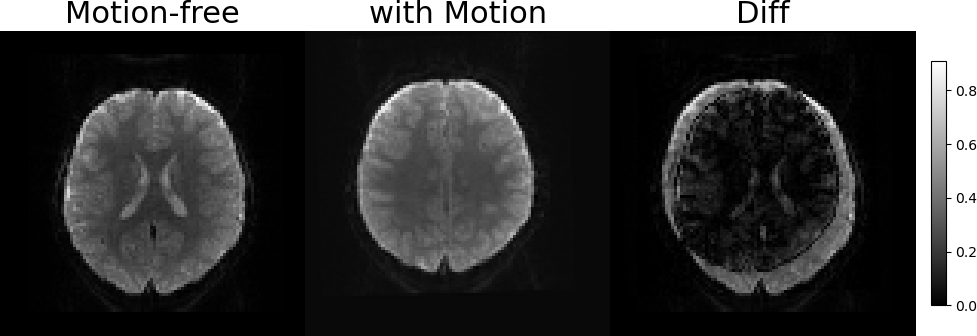

3.2 Representations of Transformations and Slices Generation

Figure 3: Illustration of the SVR problem. Two examples of free-motion volumes and volumes with synthetic motion. From left to right: Coronal LABEL:sub@fig1:a,LABEL:sub@fig1:b and Sagittal LABEL:sub@fig1:c,LABEL:sub@fig1:d views of the free-motion volumes, the generated volumes after applying the rigid transformations and sampling the slices, and the pixel-wise MSE between them, respectively. The artifacts due to the slice-level motion are visible in both Sagittal and Coronal views, however, they are not dipicted in the axial (imaging) axis of the image LABEL:sub@fig1:e,LABEL:sub@fig1:f.